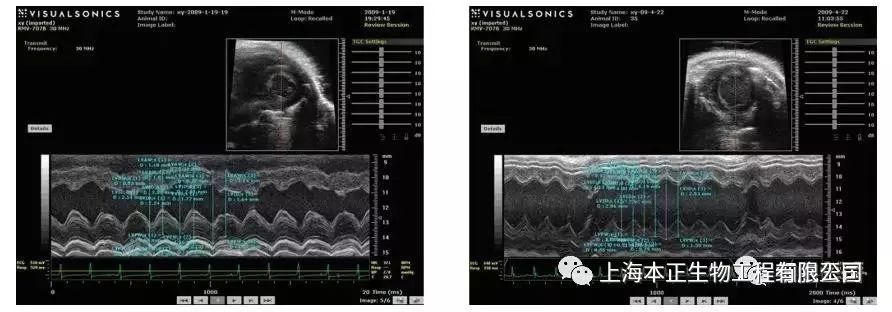

超声心动图显示对照组左室舒张期容积低于移植组